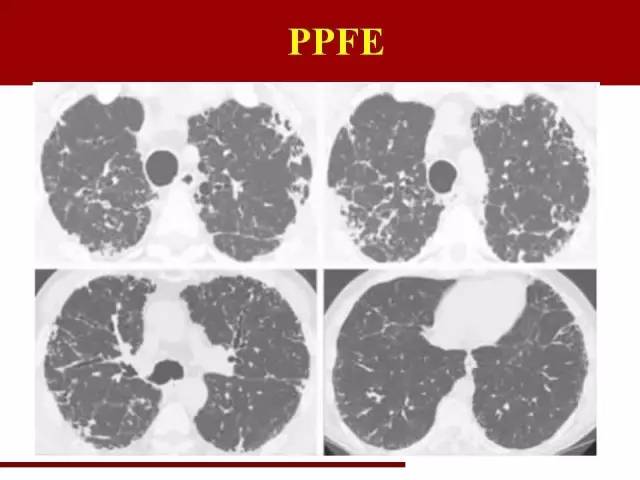

最后一类是一个年轻的间质性肺炎,2004年命名的,所以在2002年那一版分类里面没有这一类

PPFE近些年也逐渐被重视,报道逐渐增多

PPFE在间质性肺炎里面两个唯一:唯一主要同时累及肺和胸膜的间质性肺炎,唯一倾向中上肺野分布的间质性肺炎

袁怀平:

中上肺野肺纤维化伴胸膜增厚,容积缩小

需要与尘肺,特别是石棉肺鉴别

主要鉴别点在于石棉肺的胸膜斑更明显,并且伴有钙化